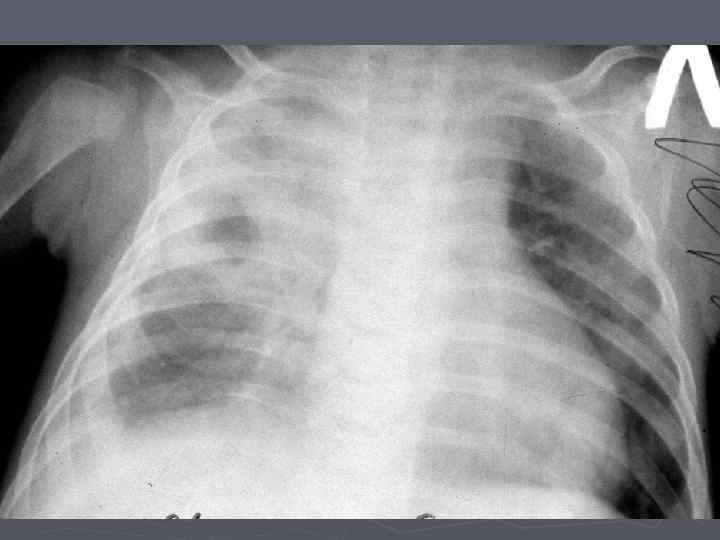

Клинические особенности туберкулеза у взрослых на фоне ВИЧ-инфекции ► ► ► ► ► Внутригрудные аденопатии; Милиарные высыпания; Частое поражение базальных сегментов легких; Относительно редкое поражение каудоапикальных сегментов легких; Распад легочной ткани диагностируется в 2 раза реже; Нередок плевральный выпот; Велика склонность к генерализации туберкулезной инфекции с множественными внелегочными локализациями. Присоеднинение туберкулезного менингита; МБТ в мокроте выявляются одинаково часто у ВИЧ негативных и позитивных лиц, по крови МБТ методом посева выделяются у 70% пациентов; При отсутствии признаков локального туберкулеза и неясной лихорадке – посев костного мозга часто дает МБТ+.

Клинико-эпидемиологические особенности туберкулезной инфекции у ВИЧинфицированных и больных СПИДом детей ► Вертикальный путь заражения ВИЧ; ► Ранний возраст; ► Семейные контакты с болеющими туберкулезом в активных фазах; ► Отсутствие вакцинации БЦЖ; ► Выраженный локальный процесс, протекающий с: § бронхолегочными поражениями; § Распадом легочной ткани; § Обсеменением легочной ткани.

Неблагоприятное сочетание ряда обстоятельств: § Ранний возраст; § Тяжелые семейные контакты; § Отсутствие вакцинации - и у свободных от ВИЧ-инфекции детей всегда приводят к развитию локального туберкулеза, протекающего, как правило, ОСЛОЖНЕННО с бронхолегочными поражениями, распадом легочной ткани, диссеминациями.